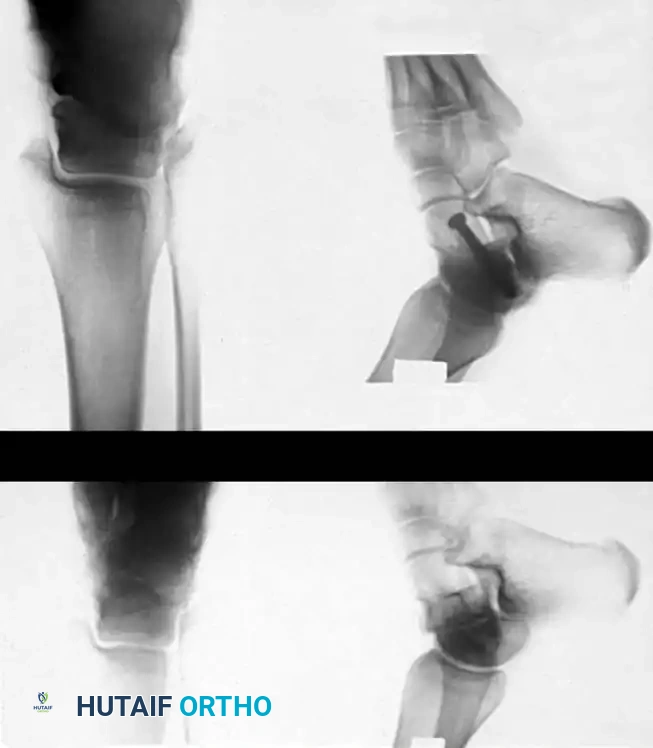

Radiographic Evaluation

Standard trauma radiographs must include anteroposterior (AP), lateral, and mortise views of the ankle, alongside an AP, lateral, and oblique of the foot.

The Canale View:

Intraoperatively and postoperatively, the Canale view is indispensable for profiling the talar neck and assessing for varus malreduction. The foot is maximally plantarflexed and internally rotated 15 degrees, with the X-ray beam angled 75 degrees cephalad from the horizontal plane.

Radiographic positioning/Canale view

X-ray example of Canale View